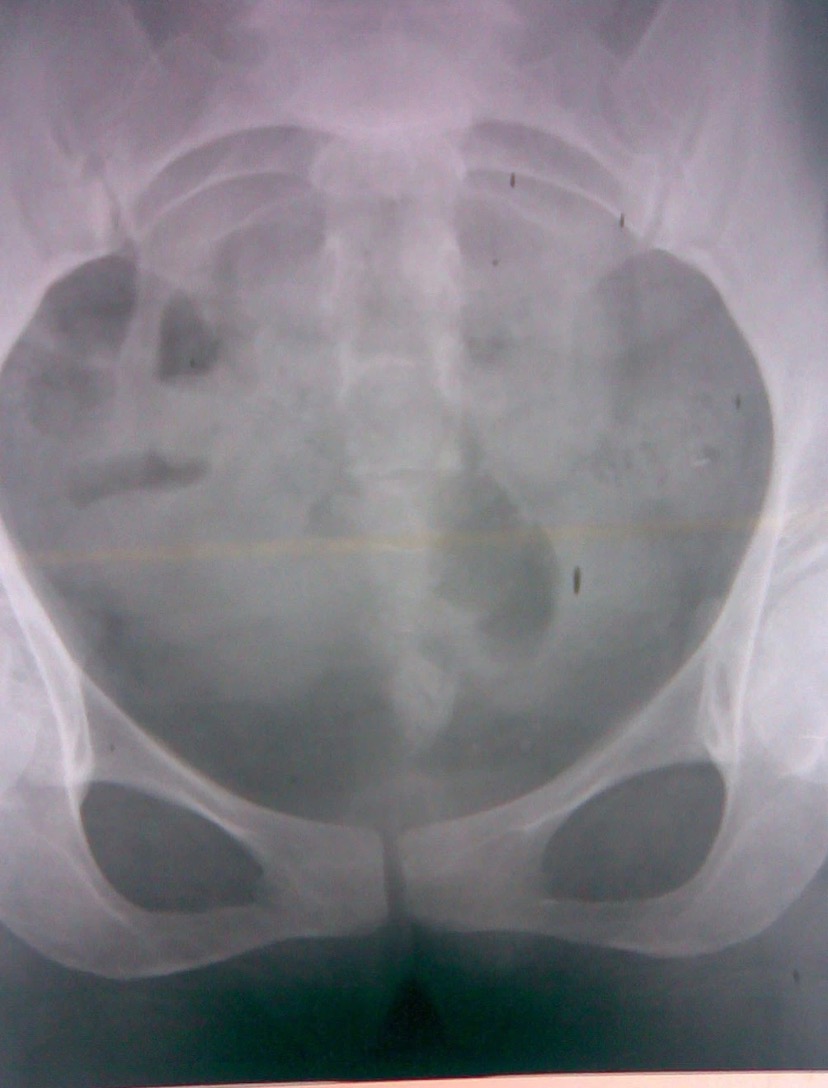

Figure 1. Рентгеновский снимок почек, мочеточника и мочевого пузыря показывает радио-непрозрачную неправильную тень на задней стенке мочевого пузыря.